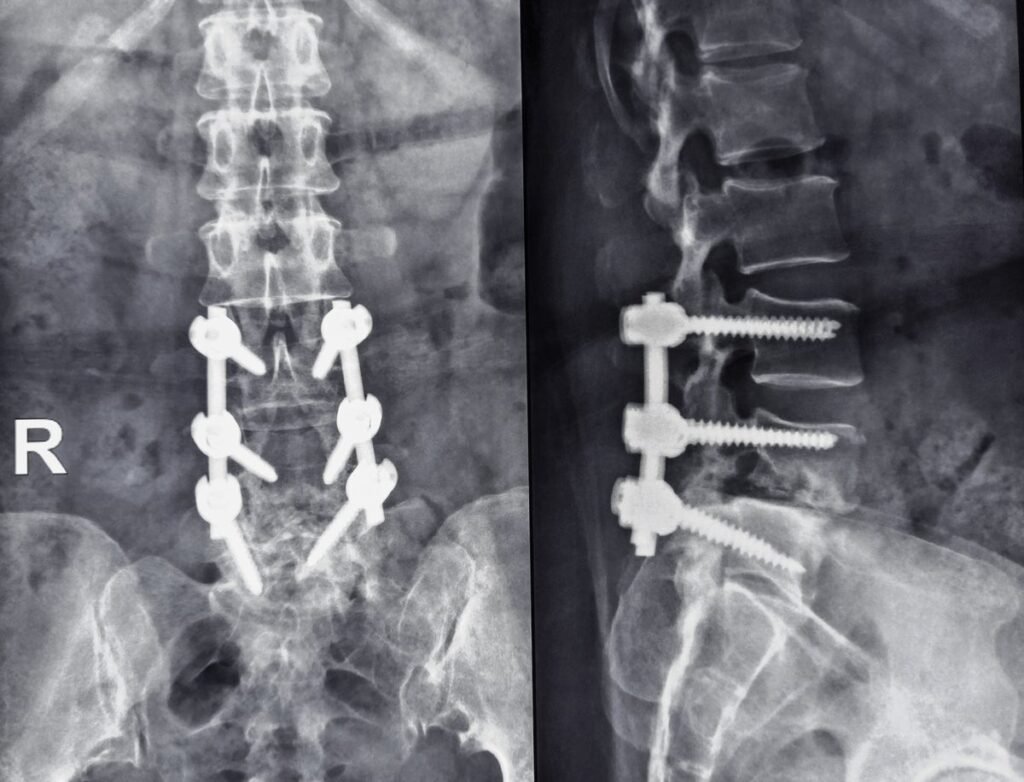

Plate and screw fixation radiograph of a human spine with lumbar spondylolisthesis beyond L4 and L5. Luigi Mangion posted a similar image on X, showing a four-bolt spine.

Luigi Mangione, the suspect charged with murder During the firing of UnitedHealthcare (UHC) CEO Brian Thompson, he suffered severe back pain allegedly caused by a condition called spondylolisthesis. Mangion told his friends The pain interfered with his ability to perform physical activities and his relationship life, according to The New York Times. He also told people that he needed surgery, and a photo at his expense in Xn (formerly Twitter) showed an apparent x-ray of a spine pierced by long rods and screws, a sign of surgery sometimes used to stabilize vertebrae if pain is not controlled by medication and physical therapy.